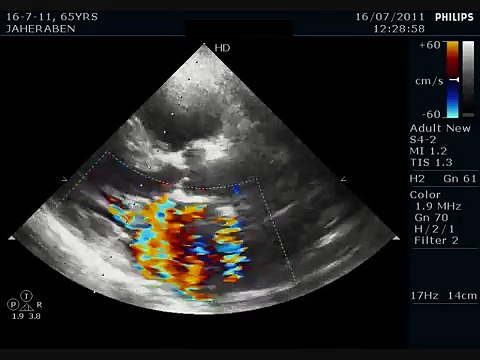

echocardiography, mitral, valve, anatomy, Pérez